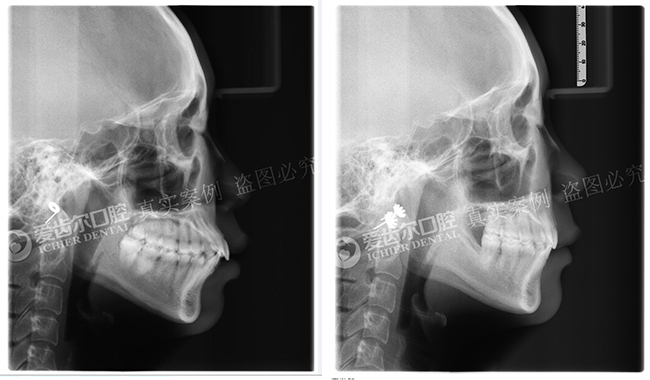

矫正前后头颅侧位片对比

经过爱齿尔口腔矫正中心田虎主任的详细检查,发现顾客的牙齿有深覆合现象,下牙牙列拥挤,需要进行牙齿拔除后再进行矫正。田虎主任与顾客进行深刻的交谈之后,精心为顾客设计了矫正方案,开始进行牙齿矫正治疗。

经过一段时间的矫正治疗,顾客的牙齿排列整齐了,面型也得到了改善,对自己的个人形象开始重视起来,现在顾客一头飘逸的长发加上温柔的笑容,是大家眼中不折不扣的女神。